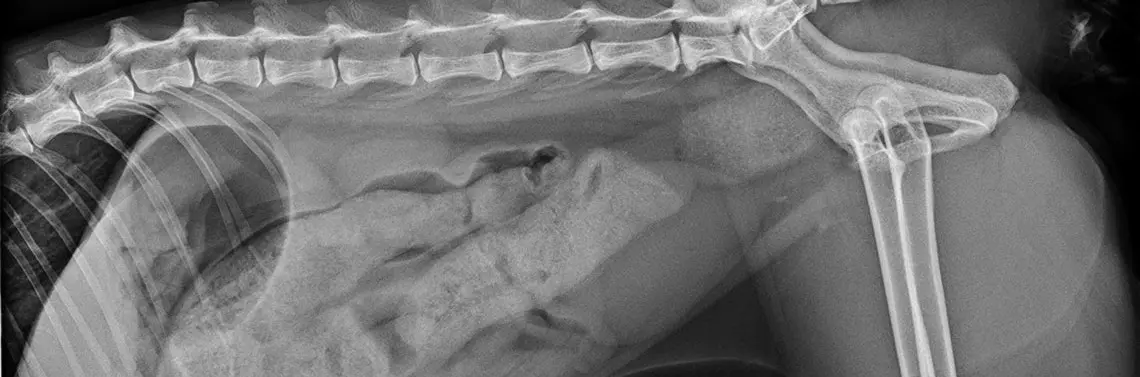

W trakcie kolejnej wizyty w badaniu fizykalnym stwierdzono koprostazę oraz obecność miękkiego guza po lewej stronie odbytnicy. Pacjenta przyjęto na leczenie stacjonarne. Wykonano badanie rentgenowskie oraz USG, w którym oprócz silnej koprostazy wykryto mniej więcej trzycentymetrową torbiel wypełnioną płynem po lewej i dogrzbietowej stronie odbytnicy. Wykonano punkcję z pobraniem płynu do badania. W badaniu cytologicznym pobranego materiału stwierdzono obecność dużej ilości komórek, głównie neutrofilów i erytrocytów, a także dużo resztkowego materiału komórkowego. Nie wykryto obecności bakterii w badaniu cytologicznym i posiewie.

Wykonano zdjęcia rent...